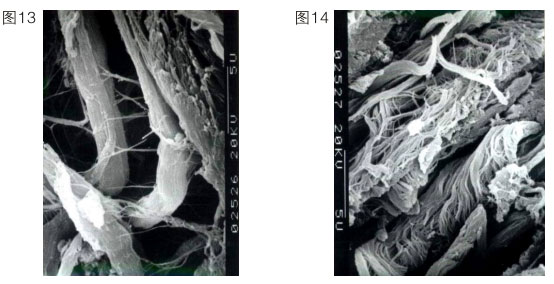

上述內(nèi)容說明再生復(fù)原重要的是要恢復(fù)其皮膚正常的生理功能。正常人的皮膚衰老了,意味著他皮膚的很多功能缺失了或退化了。因此我們的皮膚再生必須控制細胞,讓細胞強壯,恢復(fù)正常生理功能。我們在實踐中就啟動了角蛋白十九型干細胞,當(dāng)然也可以啟動角蛋白十九型以下的細胞。我們首先把表皮基底層細胞啟動起來,使它可以增加生命活力,重建,同時成纖維細胞也更新。一個90歲的老人,基底細胞只有5%是有功能的。人一旦衰老了,細胞就難以再生到足夠的數(shù)量,所以一定要保證再生物質(zhì)的量,確保細胞的功能。一般來說,成纖維細胞的功能,隨著年齡的增長會代謝低下,這個低下指的是產(chǎn)生纖維的速度減慢、產(chǎn)生的量減少,產(chǎn)生的膠原纖維不成束。一個正常細胞產(chǎn)生的纖維如左圖所示(圖13),一個衰老的細胞產(chǎn)生的纖維如右圖所示。(圖14)這個衰老的細胞產(chǎn)生的絲是雜亂無章的,沒有彈力,又散又少。人老了,在細胞里產(chǎn)生的原纖維

就雜亂無章,成纖維細胞吐出來的纖維也就不成束了。所以他的皮膚組織里面就是空洞的,皮膚就不緊致。我們再生物質(zhì)的功能就是要把這種細胞不正常的功能糾正過來。我們要增加細胞的活性。皮膚真皮的豐滿程度,是靠成纖維細胞活力的增強來實現(xiàn)的。在活力沒有增強之前先把產(chǎn)生的纖維成束,一邊成束,一邊更新。這樣就出現(xiàn)一個保持年輕復(fù)原狀態(tài)。這個皮膚再生復(fù)原的時間問題涉及代謝時間問題。表皮的創(chuàng)傷性修復(fù)速度快,一般7天修復(fù)完成。一個正常人的表皮生理代謝,則是7天一層,基底層到角質(zhì)層是30層細胞,三七二百一十天。一個完全曬黑的人經(jīng)過210天可以復(fù)原回原來的顏色。皮膚表面的黃褐斑、老年斑我們都可以解決,但不是用激光、光子消掉就可以了,這樣還會再長,因為是細胞的異常屬性沒變。我們是用再生改變這個細胞的異常屬性,激活二次生命細胞,使皮膚再生復(fù)原。